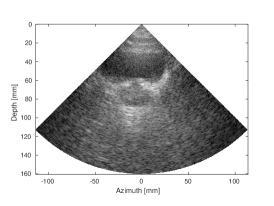

| (a) SLT | (b) MLT, (Tukey, =0.5) | (c) MLT, CNN | |

| CNR=2.33, CR=-29.33dB | CNR=1.69, CR=-19.16dB | CNR=2.2, CR= -29.24dB | |